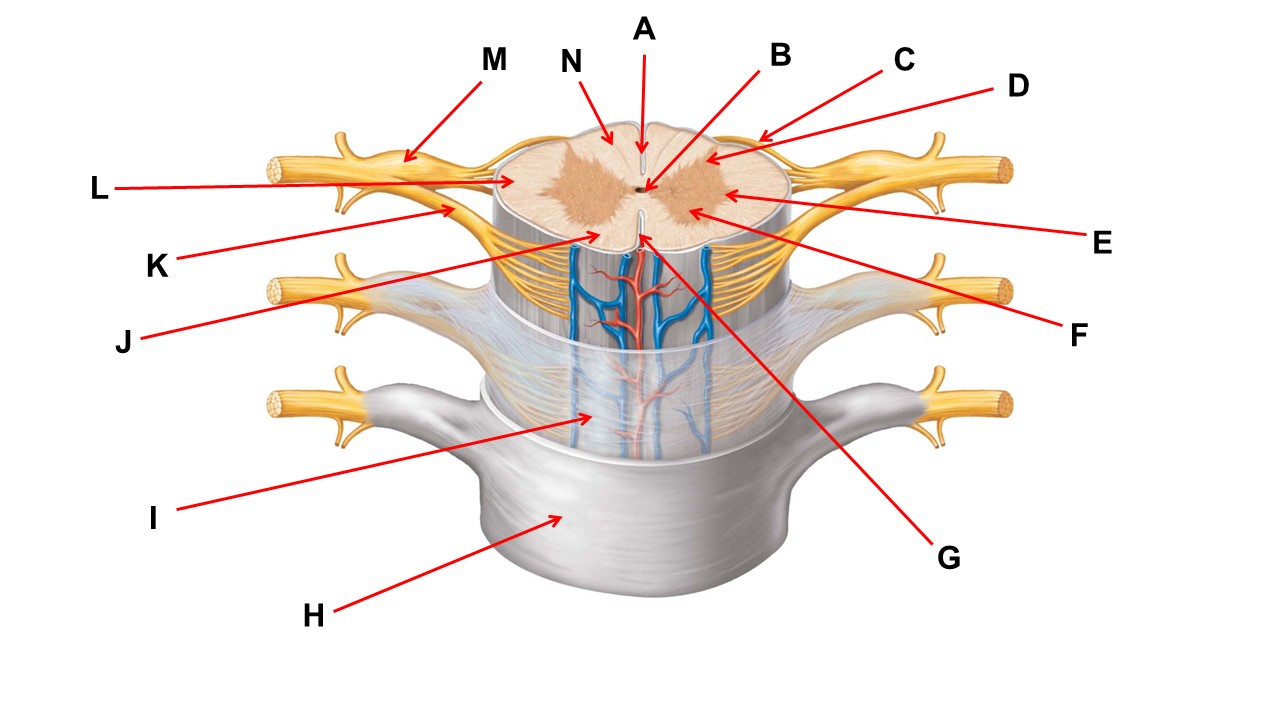

Name the region within bracket D.

Name the region of tissue surrounding the tip of arrow E.

Name the region of tissue surrounding the tip of arrow B.

Name the structure at the tip of arrow K.

ventral root

Name the region of tissue surrounding the tip of arrow J.

Name the layer at the tip of arrow I.

Name the region of tissue surrounding the tip of arrow E.

Name the region of tissue surrounding the tip of arrow N.

Name the deep groove at the tip of arrow G.

Which structure(s ) would be found in the area at the tip of arrow D.

Name the region of tissue surrounding the tip of arrow E.

Name the region within bracket G.